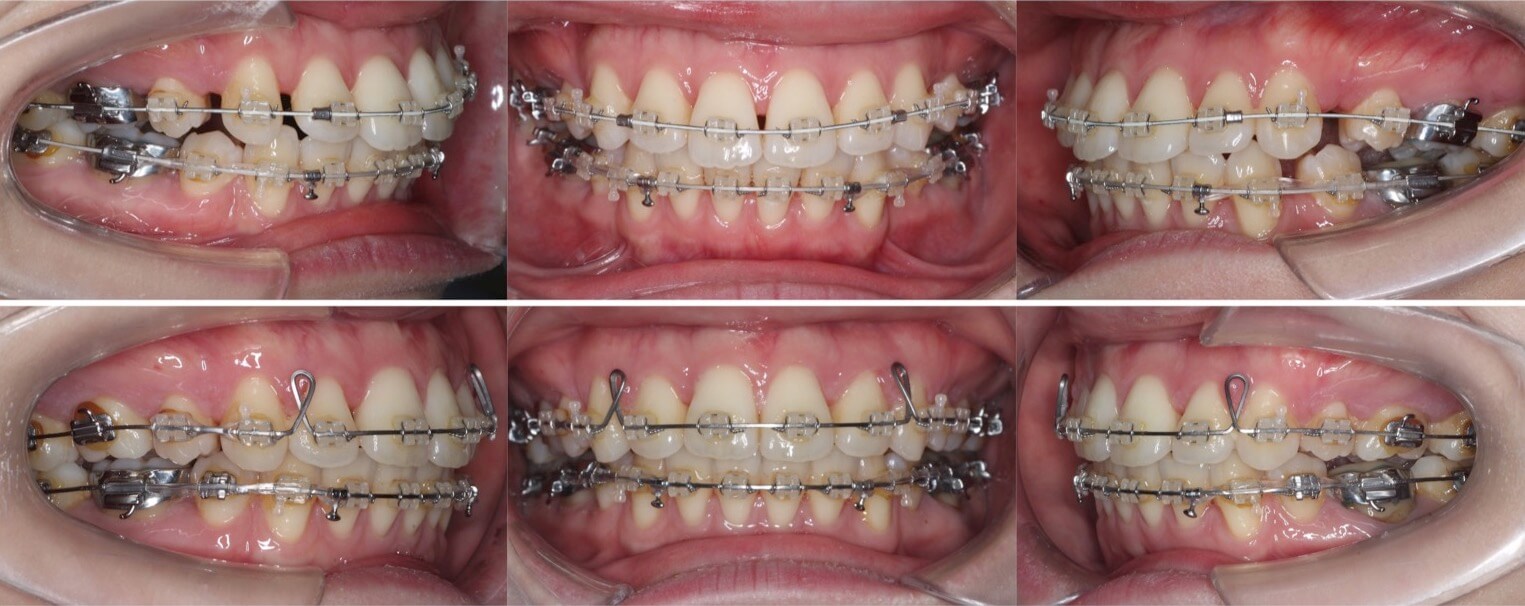

上顎前歯のトルクを加えた症例

前歯が前方に傾いている前突症例です。上下4本抜歯した空隙に、内傾させないよう上下の前歯を後方移動させました。上顎前歯のトルクコントロールは「クロージングループ」というモーメントを発生させるワイヤーを使用して行いました。

治療期間:1年9か月

リテーナー:上下プレートタイプ+フィックスタイプ

治療費用:990,000(税込)

代表的副作用:痛み・治療後の後戻り・歯根吸収・歯髄壊死・歯肉退縮